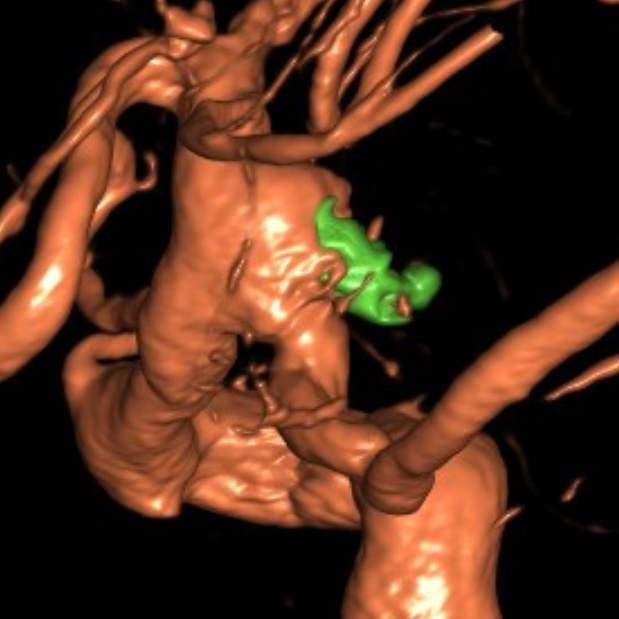

山东老年女性,2个月前遭遇颅内动脉瘤(一个血管上的不定时炸弹,不知道啥时候就爆炸了)破裂出血,病情危重。

动脉瘤经过多年修炼,形态奇葩,大动脉瘤上长着小动脉瘤,小动脉瘤上长着微小动脉瘤,还累及粗大的胚胎型大脑后动脉,经过一期单纯栓塞,消除了出血风险,老人家顺利出院康复。

近日,老人家恢复了差不多了,为了防治日后宽颈的脑动脉瘤复发,还需要稍微进行一下修修补补,减少血流对薄弱的脑动脉瘤的冲击,那就需要再简单加固一下。

这个加固的材料呢,放进血管后,慢慢会被自己的内皮细胞覆盖,变成自己身体的一部分,还能防止动脉瘤复发,是一个非常好的装备。

装备虽好,那还的找靠谱的医生给安装进去吧。今日,我们顺利为老人家在病变部位的血管植入了血流导向装置,手术顺利。然而,不是每一个破裂的脑动脉瘤患者像老人家一样这么幸运,能够有机会赶到医院,得到及时的治疗……